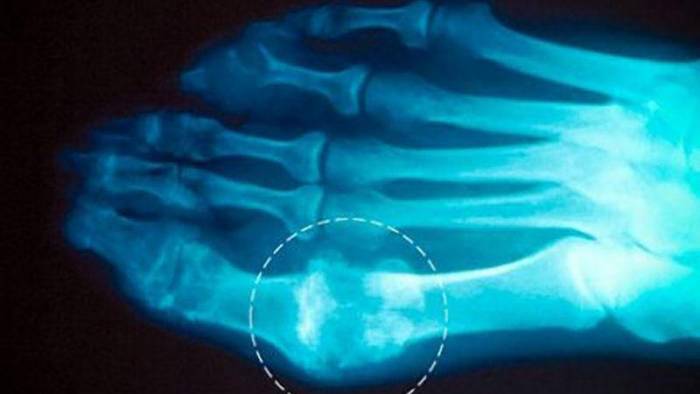

Иногда для диагностики, а также контроля подагры, используют рентгенографию и пункцию сустава с исследованием суставной жидкости. Пациенты с выявленной гиперурикемией не обязательно болеют подагрой (только 10% из них подвержены этому заболеванию).

При наличии у больного тофусов, а значит уже поздней стадии заболевания, диагностика не вызывает затруднений. Рентгеновские снимки подтвердят диагноз. На них будут видны полости в разрушенном суставе, увеличенные в размерах тени от мягких тканей. Кости будут иметь дефекты.